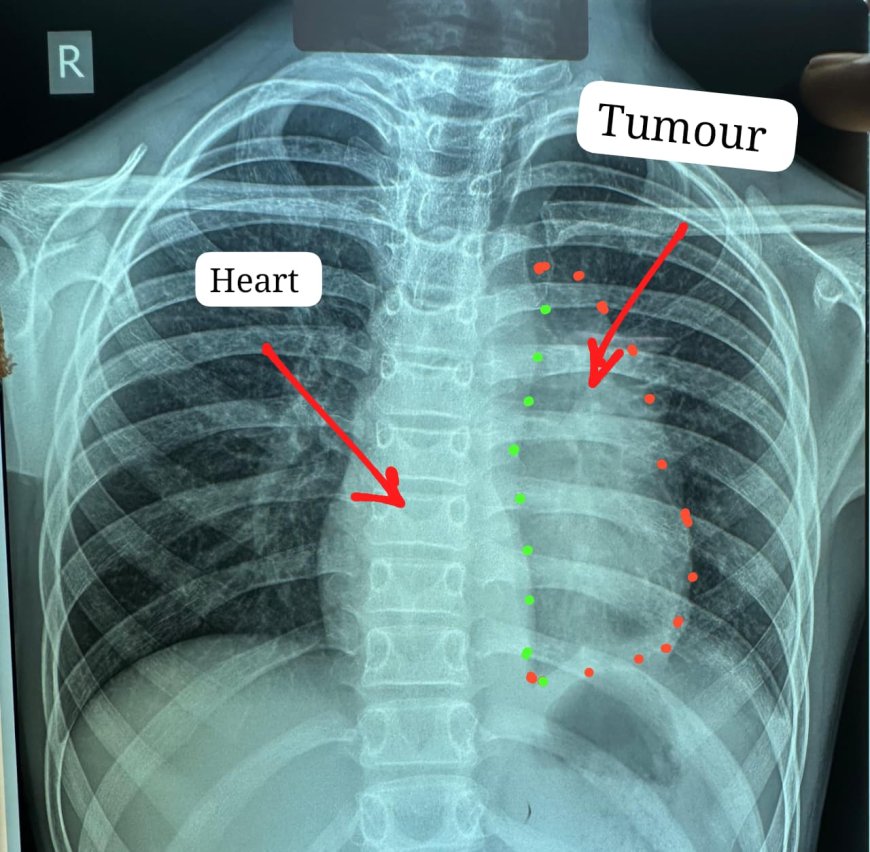

ट्यूमर ने हार्ट के साथ, पेरिकार्डियम, फ्रेनिक नर्व,महाधमनी, मुख्य पल्मोनरी आर्टरी(एमपीए), लेफ्ट एट्रियम एवं फेफड़े को अपनी चपेट में ले रखा था

डॉक्टरों के अनुसार यह ट्यूमर सामान्यतः 40 से 60 वर्ष के लोगों में पाया जाता है और बच्चों में इसका मिलना अत्यंत दुर्लभ है। यह ट्यूमर हृदय, पेरिकार्डियम, फ्रेनिक नर्व महाधमनी (एओर्टा), मुख्य पल्मोनरी आर्टरी, लेफ्ट एट्रियम और फेफड़े से चिपका हुआ था। ऐसे मामलों में ट्यूमर को पूरी तरह निकाल पाना (आर-0 रिसेक्शन) लगभग असंभव माना जाता है, लेकिन अस्पताल में उपलब्ध हार्ट-लंग मशीन की मदद से यह संभव हो पाया।

मुख्य ट्यूमर के अलावा फेफड़े की प्लूरल कैविटी में फैले तीन अन्य सैटेलाइट ट्यूमर को भी सावधानीपूर्वक निकाला गया, ताकि भविष्य में कैंसर दोबारा फैलने की संभावना न रहे। निकाले गए ट्यूमर का आकार लगभग 12x8 सेंटीमीटर और वजन करीब 400 ग्राम था।